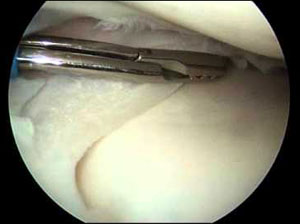

The procedure to carefully remove a damaged portion of the Meniscus is called Partial Meniscectomy. The surgeon starts by inserting the arthroscope into one of the portals. A probe is placed into the other portal. The surgeon watches on a screen while probing the Meniscus. All parts of the inside of the Knee Joint get examined.

Surgical instruments are placed into another portal and are used to remove the torn portion of Meniscus.

When the problem part of the meniscus has been removed, the surgeon checks the Knee again with the probe to be sure that no other tears are present. A small motorized cutter is being used to trim and shape the cut edge of the Meniscus. The joint is flushed with sterile saline to wash away debris from the injury or from the surgery. The portals are closed with staples.